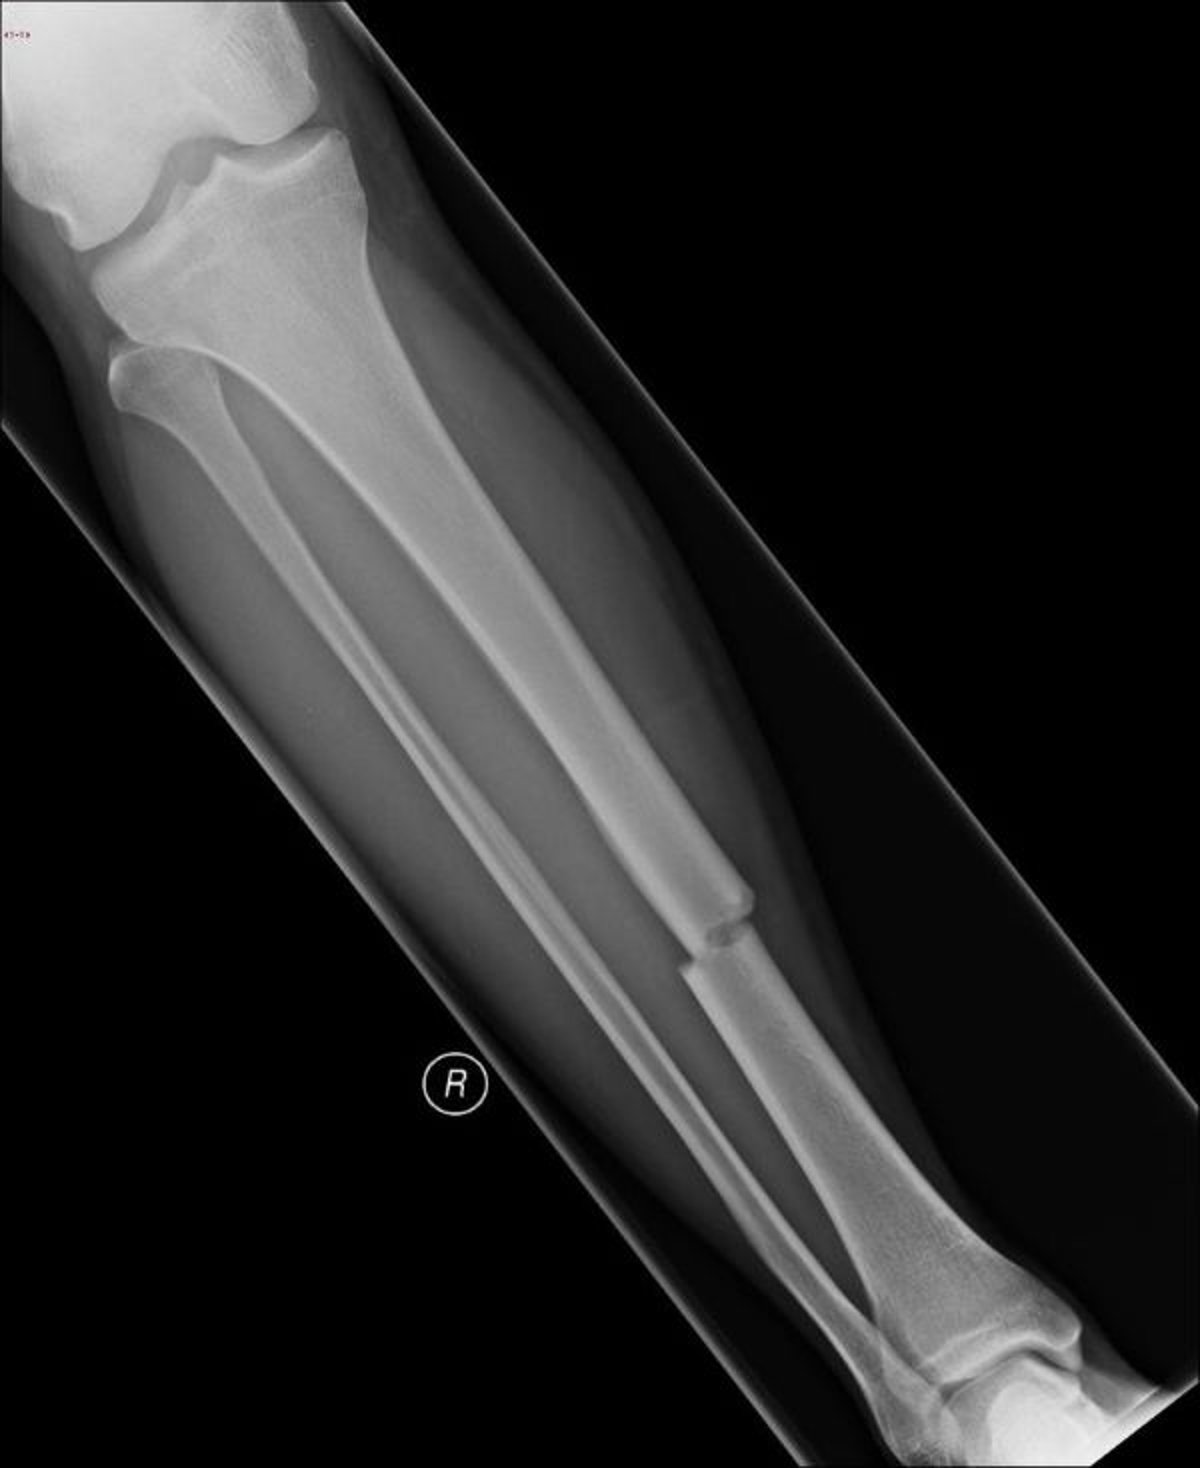

यह एक्स-रे पिंडली की हड्डी (टिबिया) बीच में टूटी हुई दिखाता है।

डैनिएल कैम्पान्ये, MD का छवि सौजन्य।